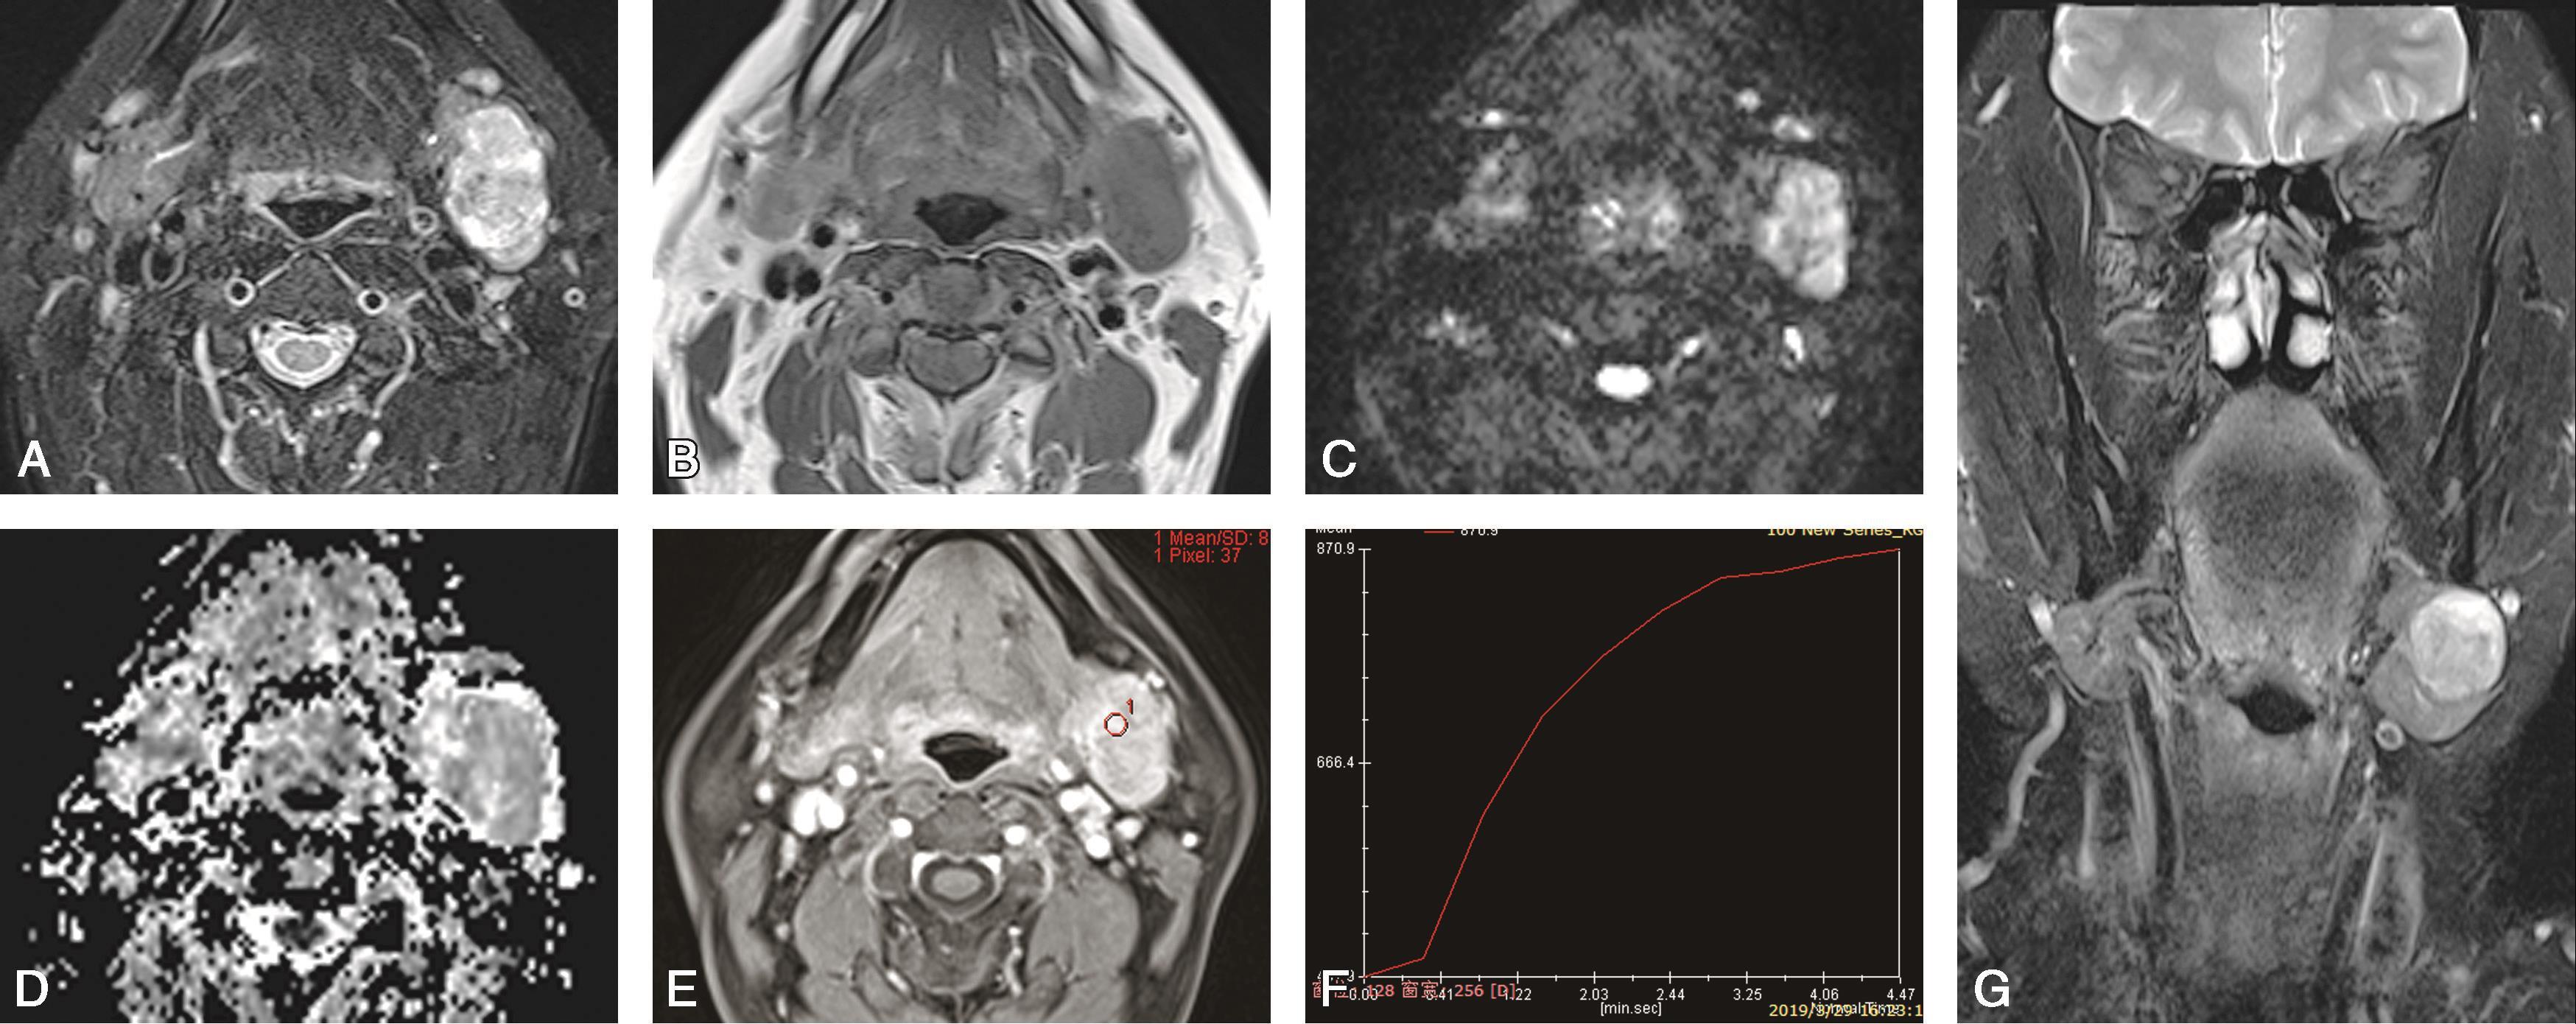

患者,男,45岁,偶然发现右侧颌下肿物1年半以上(图5-5-4)。

图5-5-4 右侧颌下腺多形性腺瘤

MRI示右侧颌下腺内一类椭圆形异常信号;轴位T

2

WI(图A)上病变以高信号为主,病灶内见稍低信号;轴位T

1

WI(图B)病变呈低信号;增强轴位(图C)、冠状位T

WI(图D)病变明显强化。